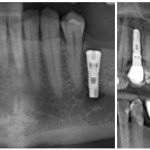

Если отсутствует один или несколько зубов, целесообразно провести дентальную имплантацию или же съемное протезирование.

Лечением патологической стираемости зубов занимаются ортопеды или стоматологи-терапевты. Основные усилия специалистов направлены на устранение этиологических причин патологической стираемости зубов, нормализацию окклюзии, восстановление твердых тканей.

В принципе, в аналогичных целях используют реставрацию пломбировочными материалами, искусственными коронками, культевыми вкладками, люминирами и винирами. Учтите, что патологическая стираемость часто связана с дефектами прикуса и требует предварительной корректировки прикуса перед протезированием.

• остановка дальнейшего стирания зубной эмали с использованием ортопедических методик: на зубы накладываются временные пластинки, коронки или протезы, повышающие высоту зубов.

Протезы используются высококачественные: литые, фарфоровые либо из очень надежной и экологически чистой пластмассы. Если имеет место частичная потеря зубов, то съемные временные протезы для борьбы с повышенной стираемостью сочетают с несъемными, которые прослужат Вам долгие годы и не будут причинять совершенно никакого дискомфорта.